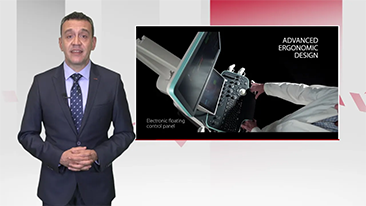

Selain kualitas gambar premium, Resona 7 juga meningkatkan kemampuan penelitian klinis dengan V Flow revolusioner untuk evaluasi hemodinamika vaskular, serta pengambilan penampang tercanggih dari rangkaian data 3D untuk diagnosis CNS pada janin. Kombinasi pengoperasian multisentuh berbasis gerakan yang paling intuitif dengan semua fitur klinis penting membuat Resona 7 menjadi gebrakan baru dalam inovasi ultrasound.